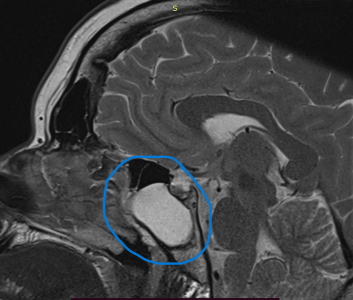

Two years ago I was diagnosed with a small pituitary tumor. It is a microadenoma. This is a tiny tumor that creates hormones. It is not cancerous but can cause chaos. We suspected that I had the tumor because of symptoms that I was having. So it wasn't a surprise when this was confirmed. However, when we did the MRI scan to find the tumor, we also found a large sphenoid sinus cyst (circled in the photo -The area that is white is supposed to empty, but it is filled with a large cyst).

On Tuesday, they are going to go up through my nose and remove the cyst completely. They will also take a more in depth look at the tumor while they are in there.